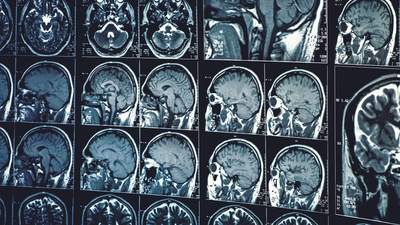

Bulguları "Proceedings of the National Academy of Sciences" dergisinde yayınlanan araştırmaya göre, ABD'deki Washington Üniversitesinden bilim insanları, 2018'de yaşları 9 ila 17 arasında değişen 160 gencin ve bu gençlerden 2021-2022'de 12 ila 16 yaşlarına erişenlerin beyinlerini manyetik rezonans görüntüleme (MRI) ile inceledi ve sonuçları karşılaştırdı.

Araştırmacılar, karşılaştırma sonucunda Covid-19 salgını döneminde sokağa çıkma yasaklarını deneyimleyen genç kızların beyninin beklenenden ortalama 4.2, genç erkeklerin beyinlerinin ise beklenenden yaklaşık 1.4 yıl daha fazla yaşlandığını buldu.

İki grubun da beynin görüşü etkileyen kısmında erken yaşlanma deneyimlediğini aktaran araştırmacılar, genç kızların beyinlerindeki değişimin 30 bölgede meydana geldiğini ve değişimlerin çoğuyla duyguların işlenmesi, yüz ifadelerinin yorumlanması ve dilin anlaşılması gibi iletişim için kritik öneme sahip olan bölgelerde karşılaştıklarını belirtti.